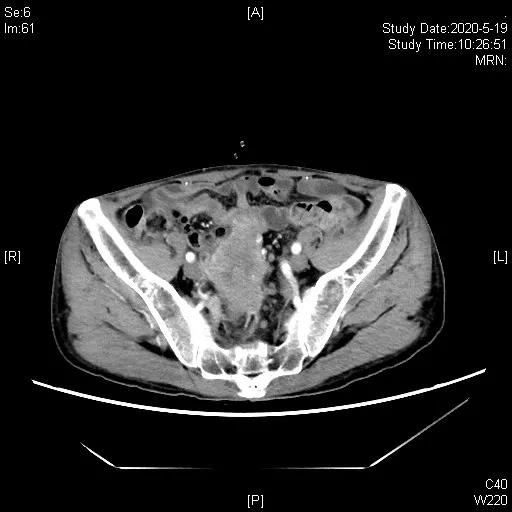

患者二线治疗后进展,TMB>10,拟行免疫治疗,鉴于患者应用抗生素不足1月(末次使用抗生素时间2020.2.20),于2020-03-25、04-21 “吉西他滨1.4d1,1.2gd8+奥沙利铂200mg”化疗2程,并于2020-03-25起,开始予以补充益生菌、调节肠道菌群联合代谢调理治疗等处理。2020-05-19,胸腹部CT示代膀胱壁增厚伴软组织肿块形成,伴双侧输尿管盆腔段受侵、双肾积水,考虑术后复发,肿块较2020-01-16老片增大,近期疗效评估疾病进展(PD),造瘘口有出血。

三线治疗3周期后,影像学评估缩小,PR